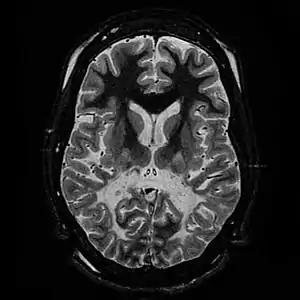

White matter, with reduced volume and increased signal intensity. The anterior white matter is spared. Features are consistent with X-linked adrenoleukodystrophy.

The Loes score is a rating of the severity of abnormalities in the brain found on MRI. It ranges from 0 to 34, based on a point system derived from the location and extent of disease and the presence of atrophy in the brain, either localized to specific points or generally throughout the brain. A Loes score of 0.5 or less is classified as normal, while a Loes score of 14 or greater is considered severe. It was developed by neuroradiologist Daniel J. Loes MD and is an important tool in assessing disease progression and the effectiveness of therapy.[12]